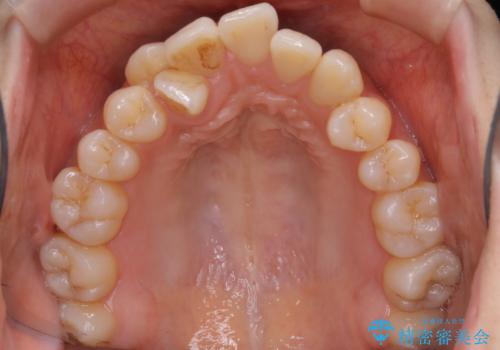

本来は外科ケース:インビザラインで前歯の重度がたつきとオープンバイトの改善

- 前歯のがたつきが気になるとご相談にいらした患者様です。矯正検査の結果、骨格的なズレが大きかったため当初の治療計画では外科矯正をご案内しました。ご本人が手術を望んでおらず、可能な限りの改善を目指すことを目標に治療を開始しました。

元々の骨格的なズレが大きかったため、当初は外科矯正をご提案していました。患者様の強いご希望により、非外科的な処置のみで可及的な改善を目指すことを目標に治療を行いました。以前よりもしっかり噛めるようになり、見た目も劇的に改善したことで大変ご満足いただけました。